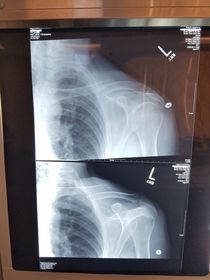

Which projections/positions are these? (top->bottom) TOP: Scapular Y-View _________________________ BOTTOM: AP External Rotation (greater tubercle in profile)